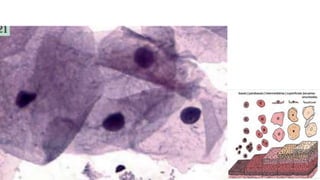

Anatomia Trato Genital Feminino

JEC - Junção EscamoColunar

Colo útero

Feminino

JEC - Junção

EscamoColunar